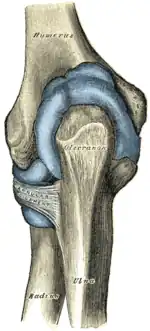

Capsule of elbow-joint (distended). Posterior aspect.

Capsule of elbow-joint (distended). Posterior aspect. -